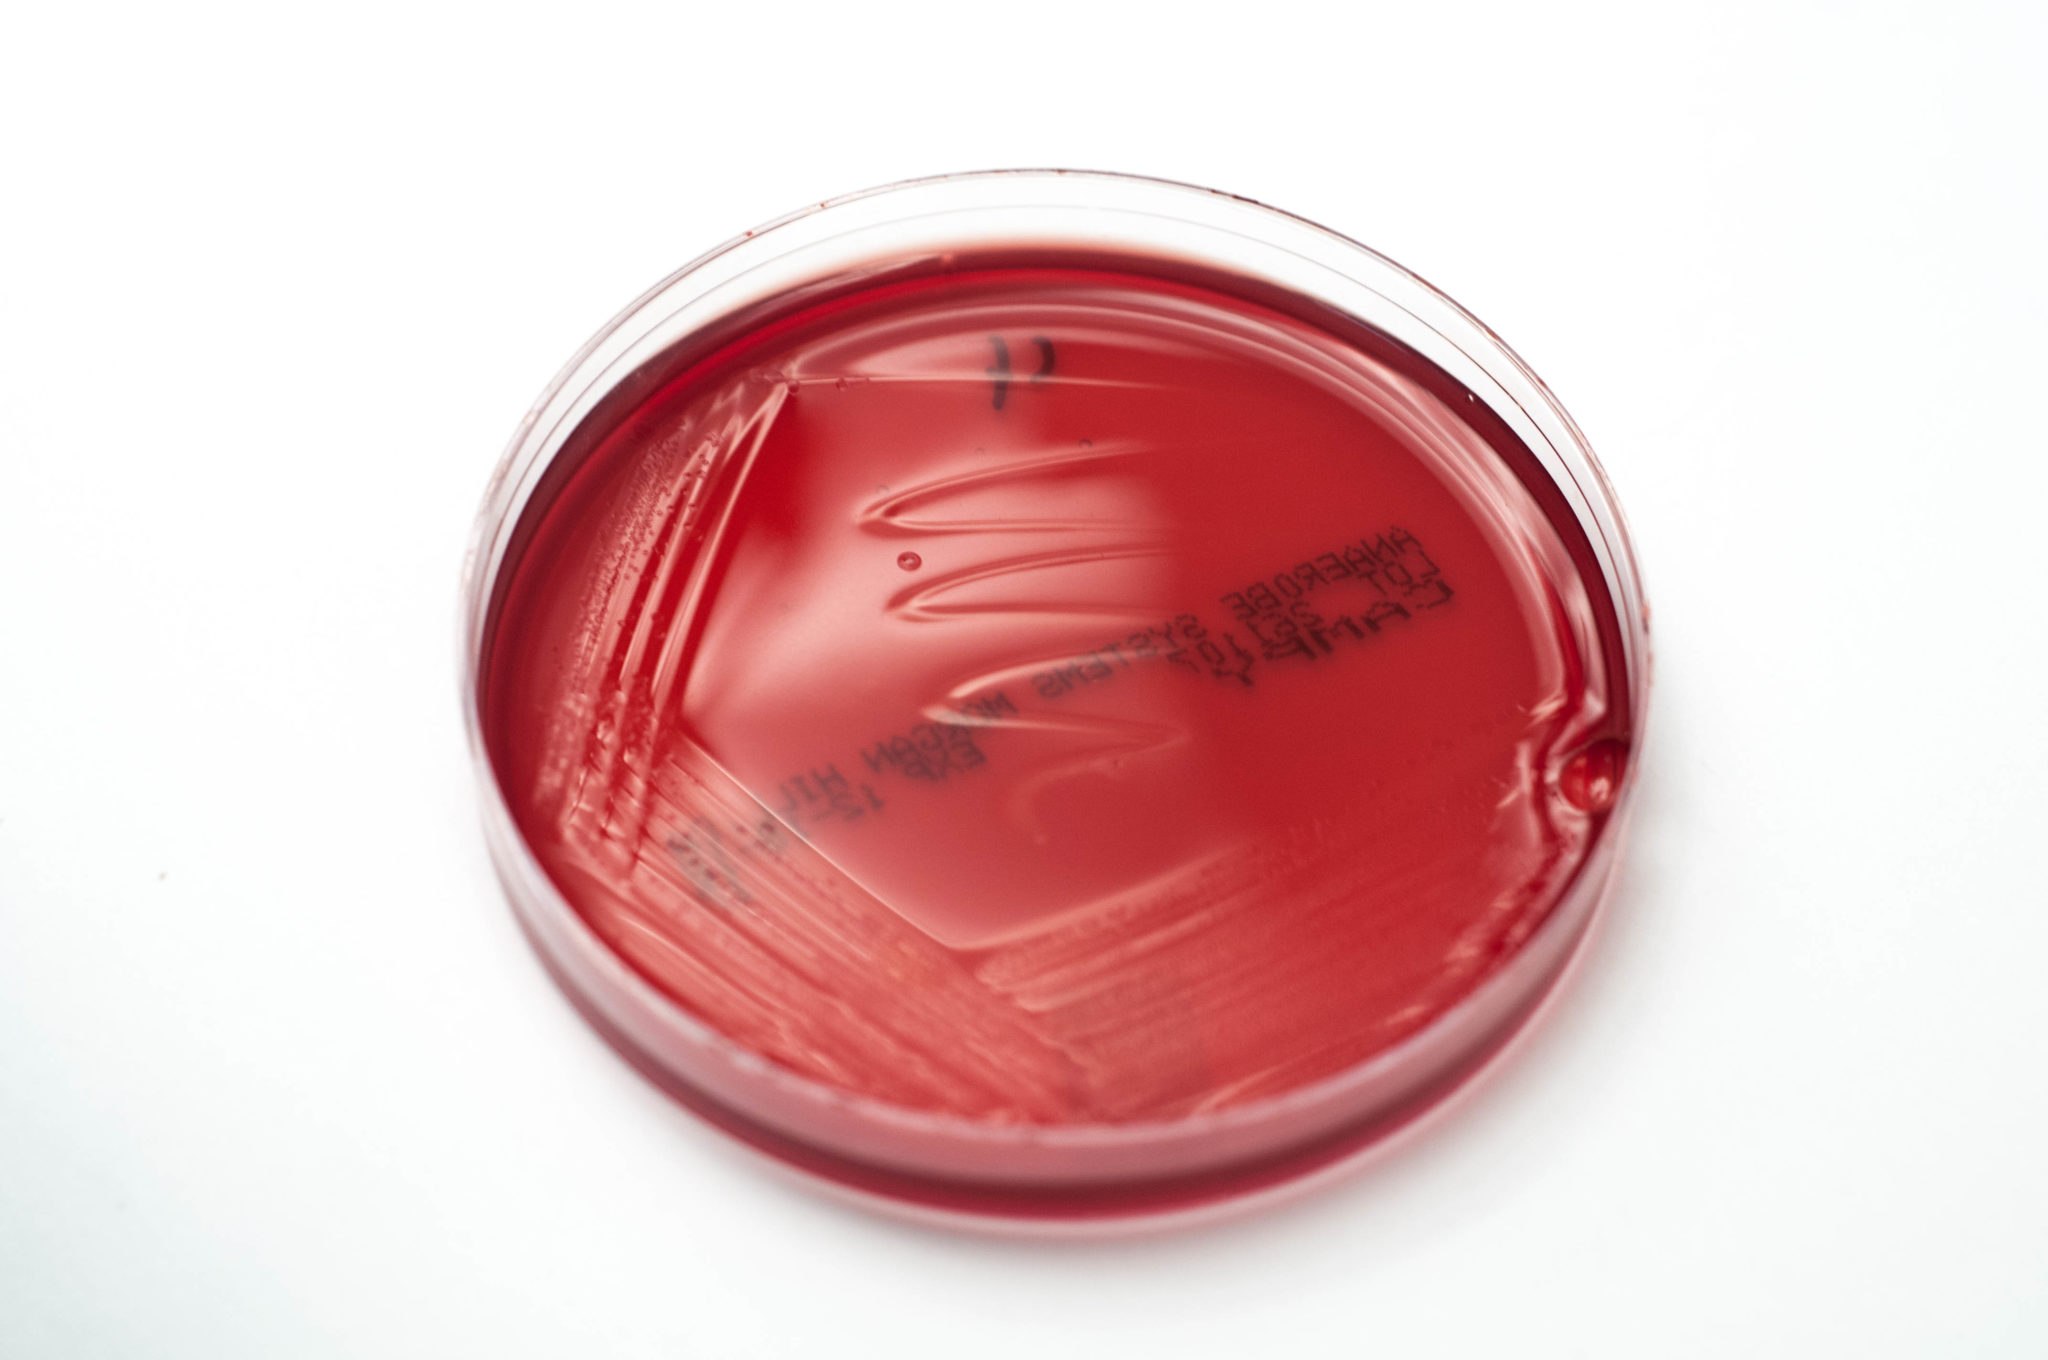

Кампилобактер фетус: патогенез и инфекции